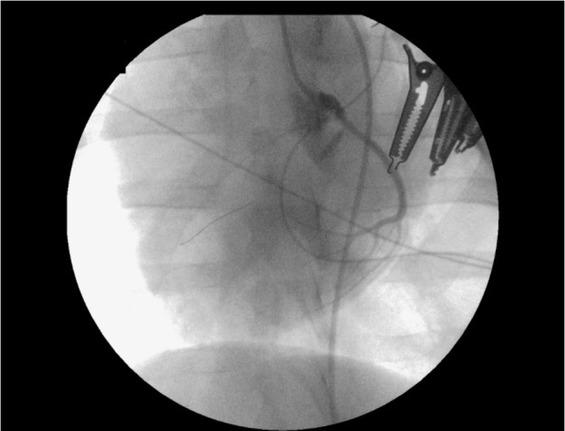

Induction of myocardial infarction. Percutaneous access to the femoral artery was obtained under ultrasound control (F37; Hitachi Aloka Medical Ltd, Mure, Mitaka-shi, Tokyo, Japan) using a 21G femoral puncture needle (21G; Balton, Warsaw, Poland) and a 6F diameter vascular introducer sheath (Balton). Following insertion of a 6F diameter Judkins Left 3.5 curvature guide catheter (Launcher; Medtronic), heparin (Heparinum WZF; Polfa Warszawa) was administered (6,000 UI), and coronary angiography was performed (Fig. 1).

Fig. 1

Coronary angiography performed on a female pig subjected to myocardial infarction induced by 30 min occlusion of the proximal part of the left anterior descending coronary artery with an angioplasty balloon in a modified anaesthetic protocol